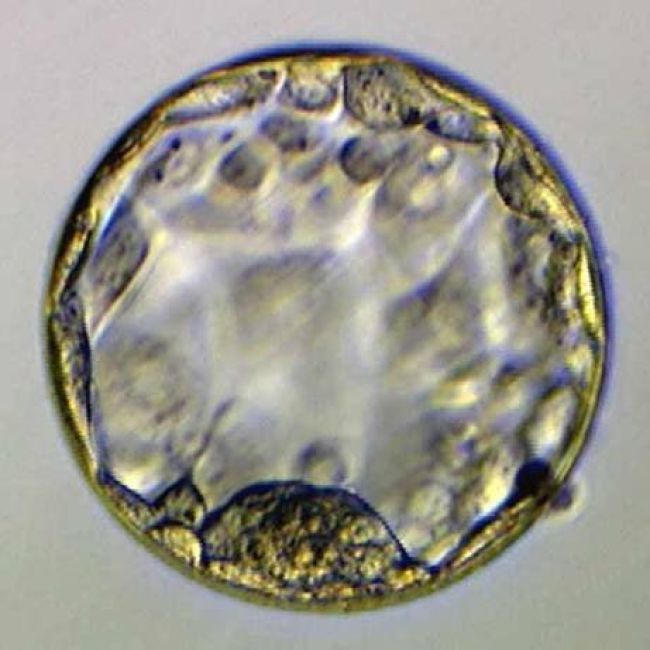

Consiste en la fertilización de los óvulos previamente extraídos de la mujer, realizados en una placa de laboratorio para transferir parte de los embriones obtenidos al útero de la mujer y conseguir que, al menos uno de ellos, logre implantarse en el endometrio.